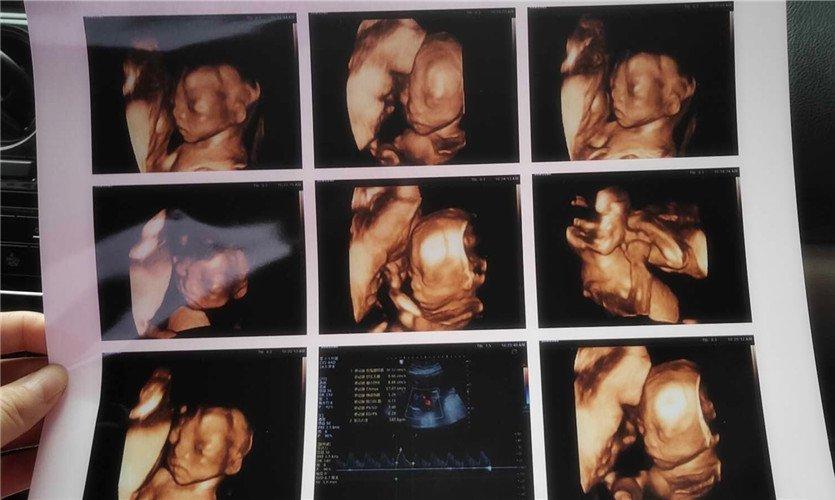

四維彩超是一種先進(jìn)的醫(yī)學(xué)影像技術(shù),通過實(shí)時(shí)觀察胎兒在母體內(nèi)的活動(dòng)情況,為醫(yī)生提供了豐富的診斷信息,在四維彩超下,我們可以清晰地觀察到胎兒的蛋蛋(睪丸)的形態(tài)、位置和大小等特征,胎兒蛋蛋是男性生殖系統(tǒng)的重要組成部分,對(duì)于胎兒的生長(zhǎng)發(fā)育具有重要意義。

在四維彩超下,胎兒蛋蛋呈現(xiàn)出特定的形態(tài)和外觀,通常情況下,胎兒蛋蛋呈現(xiàn)出圓形或橢圓形,表面光滑,內(nèi)部回聲均勻,隨著胎兒的發(fā)育,蛋蛋會(huì)逐漸增大,并呈現(xiàn)出明顯的性別特征,醫(yī)生可以通過四維彩超技術(shù),對(duì)胎兒蛋蛋的大小、形態(tài)和位置進(jìn)行評(píng)估,以判斷胎兒生殖系統(tǒng)的健康狀況。

胎兒蛋蛋的發(fā)育是一個(gè)復(fù)雜的過程,受到多種因素的影響,在胎兒發(fā)育的早期階段,蛋蛋位于腹腔內(nèi),隨著胎兒的生長(zhǎng)發(fā)育,蛋蛋逐漸下降至陰囊,這個(gè)過程受到激素、遺傳和環(huán)境等多種因素的影響,在四維彩超的觀測(cè)下,我們可以實(shí)時(shí)了解胎兒蛋蛋的發(fā)育過程,及時(shí)發(fā)現(xiàn)異常情況并采取相應(yīng)的治療措施。

四維彩超技術(shù)在評(píng)估胎兒蛋蛋發(fā)育方面具有重要意義,通過四維彩超,醫(yī)生可以實(shí)時(shí)觀察胎兒蛋蛋的形態(tài)、位置和大小等特征,了解胎兒生殖系統(tǒng)的發(fā)育情況,四維彩超還可以幫助醫(yī)生發(fā)現(xiàn)可能的異常情況,如睪丸未降、睪丸囊腫等,為及時(shí)采取治療措施提供依據(jù)。